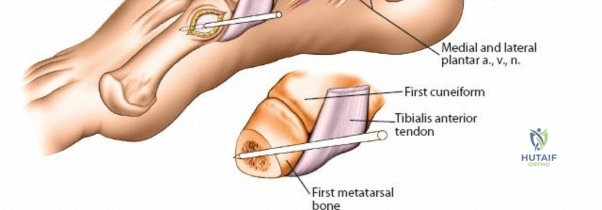

Wrist and Metacarpal Safe Zones

For spanning wrist fixators, distal pins are placed in the second metacarpal. The safe zone is the dorsoradial aspect of the second metacarpal base and shaft. The first dorsal interosseous muscle and extensor tendons must be respected. The radial artery courses proximally in the anatomic snuffbox and must be avoided during basal metacarpal pin insertion.

Metacarpal Pin Placement

1. Make two 1 cm incisions over the dorsoradial aspect of the second metacarpal.

2. Dissect bluntly, protecting the dorsal sensory branches of the radial nerve and the extensor tendons.

3. Place the tissue sleeve at a 45-degree angle to the dorsal and lateral planes to maximize purchase in the metacarpal shaft.

4. Pre-drill and insert two 3.0 mm pins.